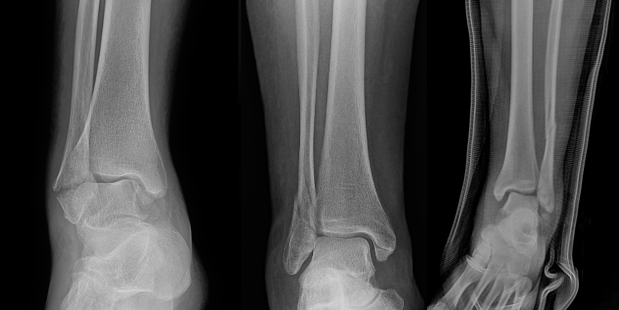

4. Posterior Malleolus Fractures Affecting Stability

Traditional fixation thresholds based solely on fragment size (>25–30% of articular surface) have been challenged. Current evidence suggests fixation should be considered when the posterior malleolar fragment contributes to articular incongruity or step-off, syndesmotic instability, posterior talar subluxation, tibial plafond impaction. CT-based assessment of fragment morphology is increasingly used to guide management.18-21 Some studies suggest fixation of the posterior malleolus, regardless of size, to restore tibiotalar joint stability and improve contact pressure distribution.7 Conversely, other studies show posterior malleolar fixation in trimalleolar ankle fracture increases overall morbidity with increased tourniquet time, and wound healing complications, and did not eliminate the need for syndesmotic fixation.22 Literature supports a shift away from fragment size, and toward CT-guided, morphology and stability driven decision making for posterior malleolar fixation, recognizing potential benefits in tibiotalar stability while acknowledging increased operative morbidity and inconsistent avoidance of syndesmotic fixation (Figure 4).